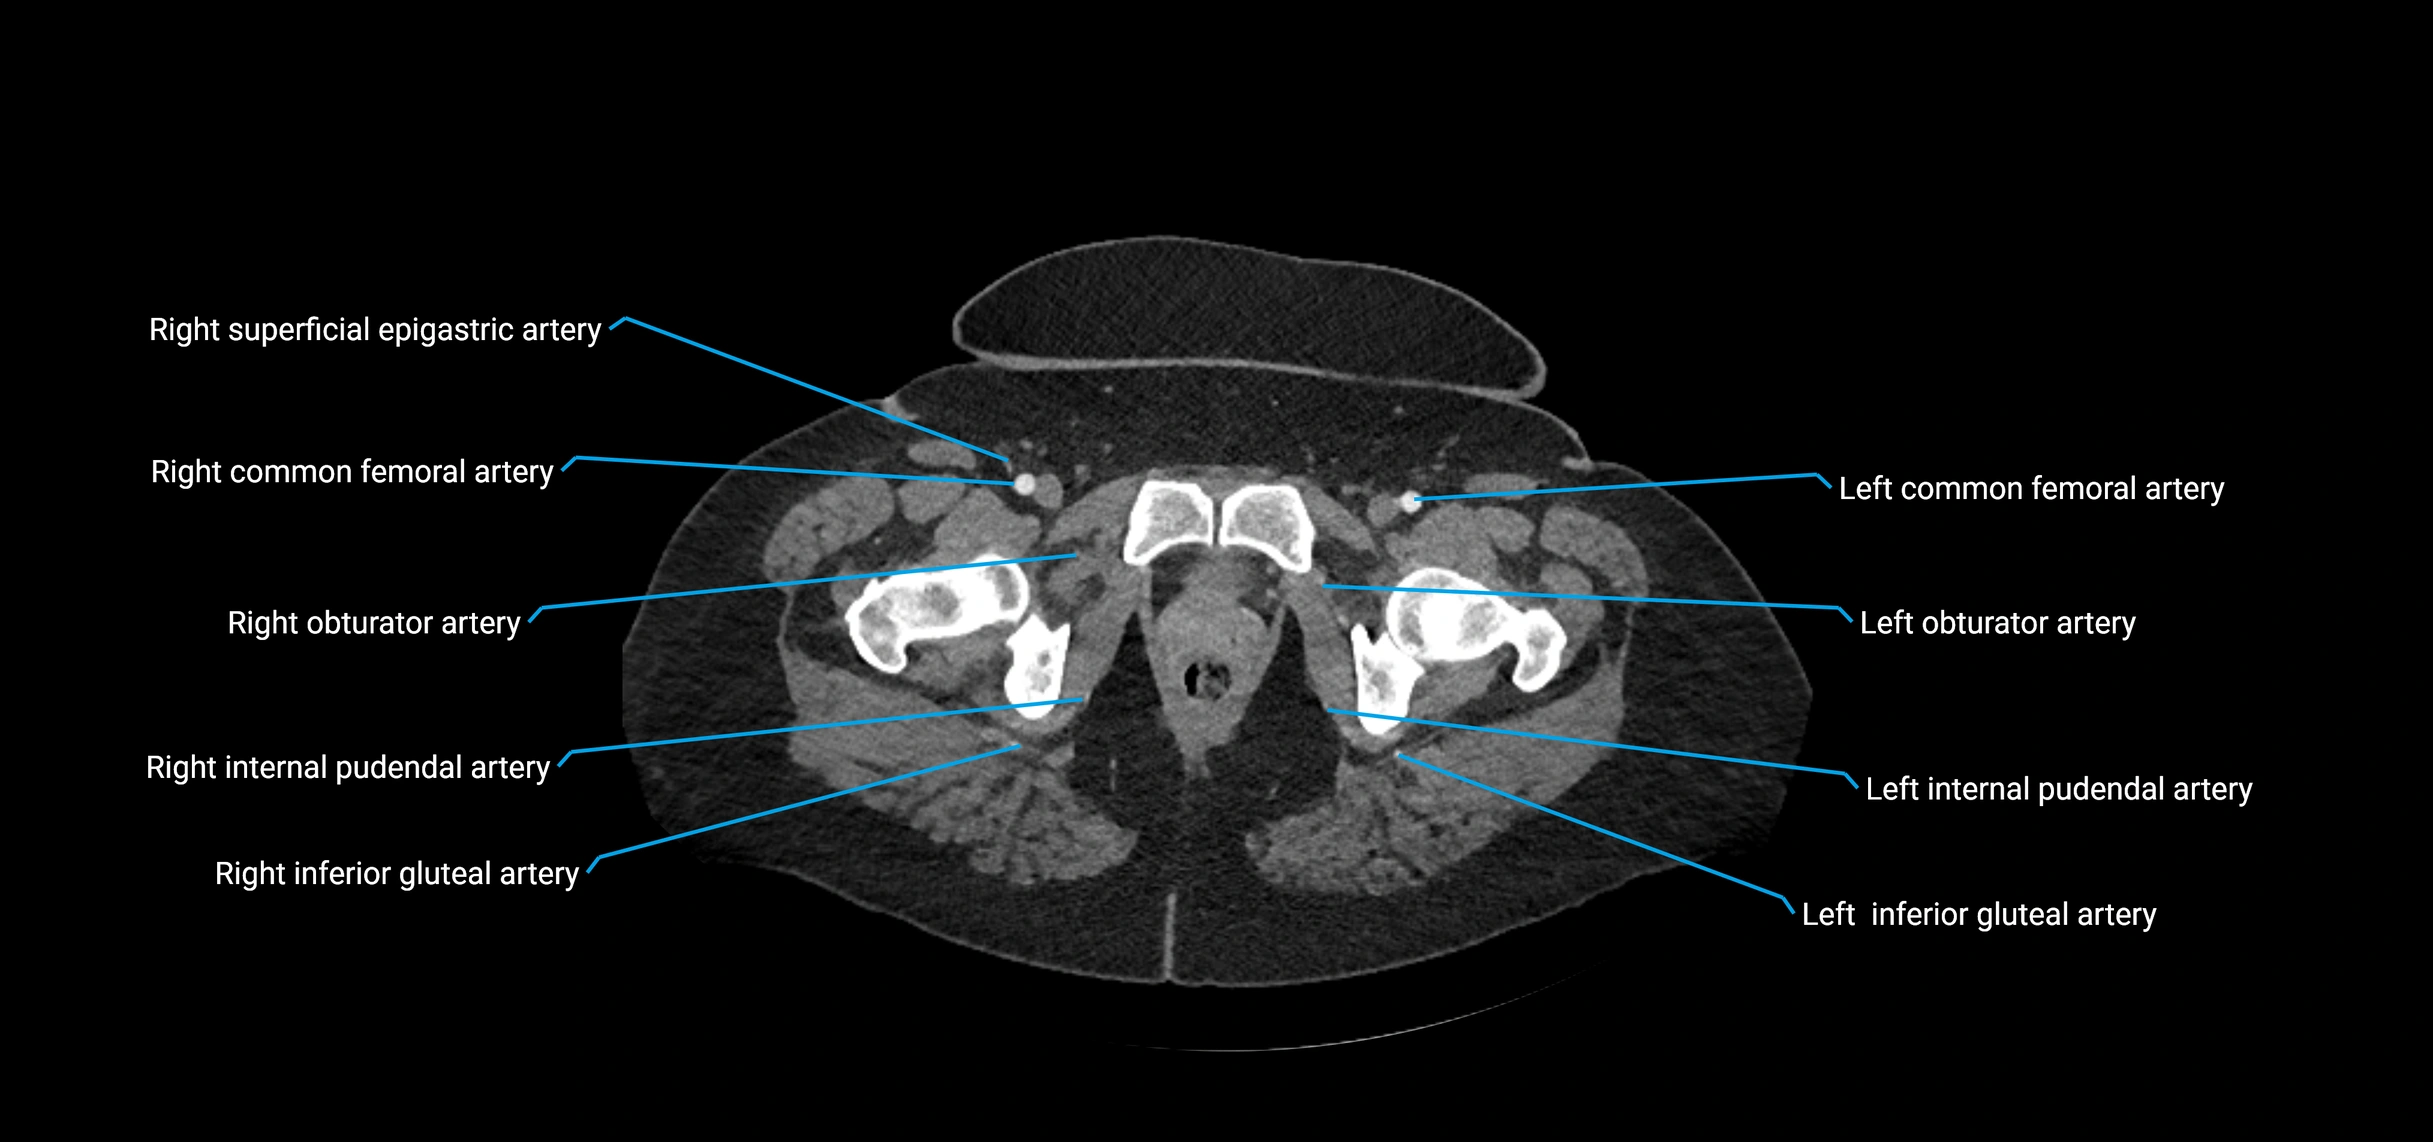

Branches

• Parietal branches: inferior phrenic arteries, lumbar arteries, median sacral artery

• Terminal branches: right and left common iliac arteries

CT Appearance

Contrast-enhanced CT (CTA):

• Gold standard for abdominal aortic imaging

• Provides excellent detail of lumen, wall, aneurysm, thrombus, and branch vessels

• Multiplanar and 3D reconstructions help in aneurysm measurement, stent graft planning, and dissection evaluation

CT images

image